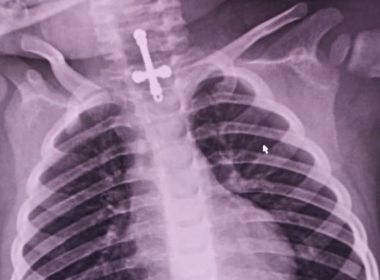

Um garoto de 2 anos segue internado depois de fazer uma intervenção médica para retirar um crucifixo que ele engoliu no último sábado (17), em Divinópolis (MG). O objeto obstruiu o sistema digestório do garoto, que foi inicialmente hospitalizado na Unidade de Pronto Atendimento (UPA) em Divinópolis.

Assim que a vaga foi disponibilizada, o menino foi levado para uma unidade hospitalar no município de Passos, no Sul de Minas, onde o objeto foi retirado.

Por conta do tempo de permanência do objeto no organismo da criança, ele apresentou febre em decorrência de uma infecção após a retirada do crucifixo. O garoto segue recebendo tratamento medicamentoso até ter alta; ainda não há previsão de liberação da criança.